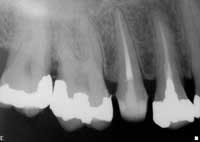

Inherent in a discussion of profitability and the accomplishment of the aforementioned steps, is the need to have the best possible equipment at hand to promote the most efficient and ergonomic treatment possible. In years past, this equipment might include the SystemB (SybronEndo, Orange, Calif.) and Obtura II (Spartan Obtura, Fenton, Mo.) to facilitate a thermosoftened obturation into all the ramifications of the root canal system. Today, there is the state-of-the-art Elements Obturation Unit (SybronEndo, Orange, Calif.) that combines and enhances each of these pieces of equipment separately. The Elements Obturation Unit is a machine that has a SystemB styled heat source on one side, and an extruder for gutta percha, RealSeal or Resilon on the other. This single unit contains, in one sleek and ergonomic design, all the functionality needed to obturate canals with the various warm methods of obturation. The clinician can perform SystemB obturation, the classic vertical compaction of warm gutta percha, or a combination of procedures (Fig. 4). On the heat source side, the heat can only be turned on for four seconds when the heat source is activated. As a result, there is minimal risk of damage to the periodontal ligament. On the extruder side, the cartridges that contain RealSeal or gutta percha are single use, self-contained, and very convenient. RealSeal cartridges are less expensive than carrier-based products and more expensive than gutta percha. Resilon technology also is available on Simplifil devices (LightSpeed Technologies, San Antonio, Texas).